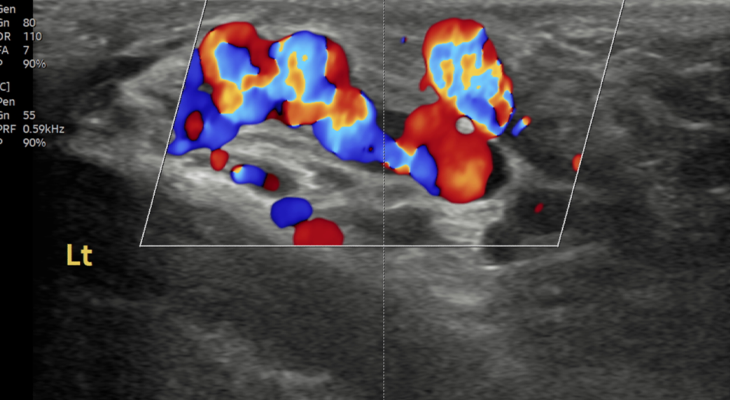

투석혈관 협착,

스텐트삽입술

시술 전

시술 후

투석중 혈류 저하,

풍선확장술로 회복

수술 후 재발된

정계정맥류 시술로 재치료